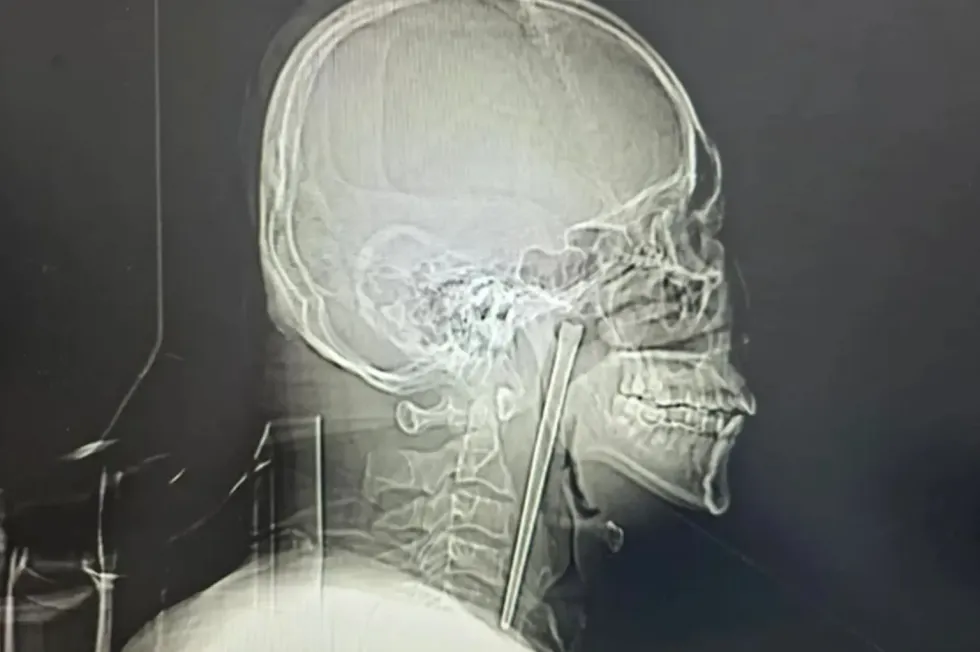

A Chinese man endured eight years with a metal chopstick lodged in his throat after swallowing the utensil during a drunken meal in 2018.

Mr Wang, a 46-year-old described as an "alcoholic" in a hospital case study published in March, initially sought medical attention shortly after the incident but declined treatment.

He did not want surgeons to slice open his neck to retrieve the five-inch object.

A Chinese man endured eight years with a metal chopstick lodged in his throat after swallowing the utensil during a drunken meal in 2018

Surgeons successfully extracted the chopstick using a minimally invasive technique through Mr Wang's mouth.

He did not want surgeons to slice open his neck to retrieve the five-inch object

This meant there was no need for a neck incision.

Dr Huang Weipeng, who treated the patient, recalled his astonishment upon learning the timeline: "He told us a chopstick was trapped in his throat.

"I thought it happened just now, but he said this was eight years ago."

Neither Mr Wang's vocal cords nor the surrounding mucous membrane sustained any injury from the prolonged presence of the metal object.

Both functioned normally following the operation.